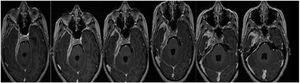

Discusión de las imágenesEn los estudios sucesivos de resonancia magnética se evidencia tejido patológico que engrosa las meninges con un espesor de 19,5mm, y que muestra señal isointensa en T1, hipointensa en T2 y tiñe con el contraste con moderada restricción a la difusión del agua.

Compromete la base de cráneo en topografía parasagital derecha, con extensión hacia el conducto carotídeo, foramen yugular, agujero rasgado posterior, peñasco y tienda del cerebelo homolateral. Invade. Además. el conducto auditivo interno, el seno cavernoso y el vértice de la órbita derecha, con compromiso paquimeníngeo a nivel de la fosa temporal profunda rodeando circunferencialmente los pares craneales III, V, VI, segmento cisternal e intracavernoso, VII y VIII a nivel del conducto auditivo interno.

Se observa progresión de la paquimeningitis con compromiso de la región anterior del quiasma óptico, el cual se observa engrosado con refuerzo poscontraste. Reemplaza a la vena yugular interna derecha en su foramen, no evidenciándose opacificación del segmento proximal de la misma. Defecto de relleno parcial del seno sigmoideo homolateral.

Comparativamente se observa respuesta parcial al tratamiento instaurado con relación al estudio de base con espesor paquimeníngeo de 19,5mm al inicio; en los controles presenta disminución de 10,5mm (53% del tamaño inicial) a la semana del pulso de corticoides; a 8,7mm (44% del inicial) con corticoides más rituximab; y en el último control, luego de 3 meses del inicio del tratamiento, con corticoterapia de mantenimiento 10mg/día de prednisona y metotrexato presenta 7,8mm (40% del tamaño inicial) (figs. 3A-D).

Secuencias en T1 de la RMN sucesivas en la evolución de la paciente. Desde (A) lesión basal con engrosamiento de aproximadamente 2cm, hasta (D) estado posterior al tratamiento con esteroides y rituximab que evidencia la mejoría franca del engrosamiento y el edema. E) Cortes tardíos que muestran zonas de fibrosis.

En el último control se observa disminución del engrosamiento paquimeníngeo descrito en los estudios anteriores, a nivel del quiasma, del conducto auditivo interno, del seno cavernoso, y espesor de fosa temporal; y al realizarse cortes tardíos a los 30min se identifica mayor realce del tejido paquimeníngeo en relación a componente fibrótico (fig. 3E).